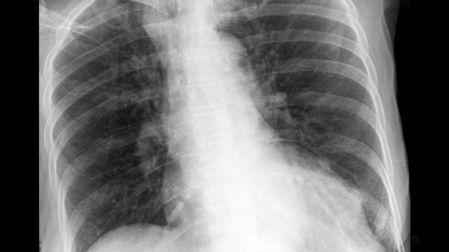

El diagnóstico suele requerir radiografías de tórax o tomografías computarizadas (TAC) donde se observan nódulos o masas de tejido fibroso. En etapas avanzadas, la silicosis aumenta drásticamente el riesgo de desarrollar tuberculosis, cáncer de pulmón y enfermedades autoinmunes como la esclerodermia.